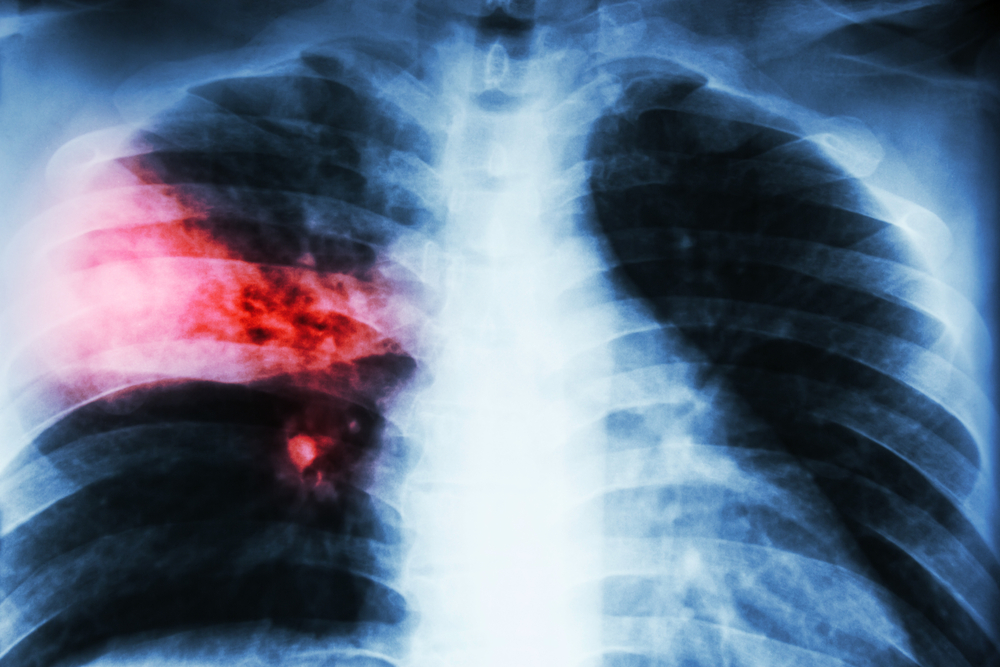

ডা. আব্দুস শাকুর খান বলেন, ফুসফুসের ক্যানসার হচ্ছে ফুসফুসের এক ধরনের টিউমার। অর্থাৎ ফুসফুসের যে স্বাভাবিক কোষ আছে সেই স্বাভাবিক কোষের যখন অস্বাভাবিক এবং অনিয়ন্ত্রিত বৃদ্ধি হয়ে চাকার মত সৃষ্টি করে, তাকেই ফুসফুস ক্যানসার বলে। এটি শরীরের জন্য মারাত্মক ক্ষতিকর। ক্যানসার যখন ফুসফুসে হয় এটা শুধু নির্দিষ্ট জায়গায় থাকে না বরং অস্বাভাবিক এবং অনিয়ন্ত্রিত বৃদ্ধির কারণে শরীরের অন্যান্য অংশেও ছড়িয়ে পড়ে। সঠিক সময়ে শনাক্ত ও যথাযথ চিকিৎসার অভাবে শেষ পর্যন্ত মৃত্যুরও কারণ হয়ে থাকে।

ফুসফুস ক্যানসারের অন্যতম লক্ষন হচ্ছে দীর্ঘমেয়াদী কাশি হওয়া, কখনো কখনো কাশির সঙ্গে কফ এবং কফের সঙ্গে রক্ত যাওয়া। ফুসফুসের ক্যানসারের কারণে বুকে ব্যথা হতে পারে। ক্যানসার যদি ব্যাপকতা পায় এবং বুকে পানি চলে আসে অথবা ফুসফুসে বেশি ছড়িয়ে পড়লে শ্বাসকষ্ট হতে পারে। এছাড়া কিছু সাধারণ লক্ষণ আছে, যেগুলো সব ক্যানসারেই দেখা যায়। যেমন- ওজন কমে যাওয়া, খাবারে অরুচি।